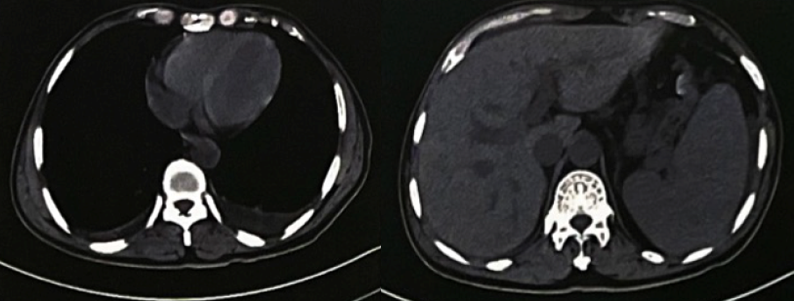

查腹部CT

(图2):脾肿大,局部斑片状低密度影,梗死可能性大;食管胃底静脉曲张(脾静脉明显增宽,胃底部静脉局部增粗扭曲)。

图2 腹部CT